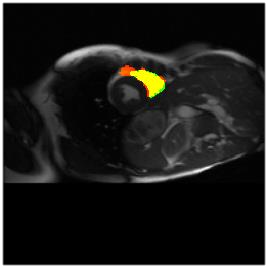

Deep Convolutional Neural Networks (DCNNs) are used extensively in biomedical image segmentation. However, current DCNNs usually use down sampling layers for increasing the receptive field and gaining abstract semantic information. These down sampling layers decrease the spatial dimension of feature maps, which can be detrimental to semantic image segmentation. Atrous convolution is an alternative for the down sampling layer. It increases the receptive field whilst maintains the spatial dimension of feature maps. In this paper, a method for effective atrous rate setting is proposed to achieve the largest and fully-covered receptive field with a minimum number of atrous convolutional layers. Furthermore, different atrous blocks, shortcut connections and normalization methods are explored to select the optimal network structure setting. These lead to a new and full-scale DCNN - Atrous Convolutional Neural Network (ACNN), which incorporates cascaded atrous II-blocks, residual learning and Fine Group Normalization (FGN). Application results of the proposed ACNN to Magnetic Resonance Imaging (MRI) and Computed Tomography (CT) image segmentation demonstrate that the proposed ACNN can achieve comparable segmentation Dice Similarity Coefficients (DSCs) to U-Net, optimized U-Net and hybrid network, but with significantly reduced trainable parameters due to the use of full-scale feature maps and therefore computationally is much more efficient for both the training and inference.